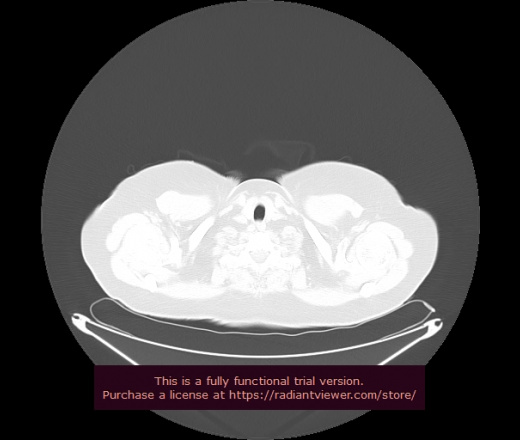

Уважаемые коллеги, если имеется интерес, сможете ли Вы спрогнозировать дальнейшее +-одинаковое течение процесса у 4 данных разных пациентов? Зацепиться где-то можно очень просто, где-то нельзя.